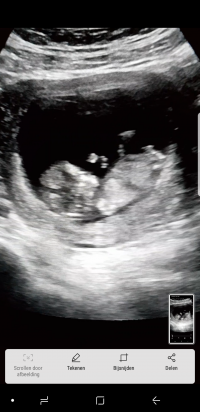

Merhaba araniza yeni katildim 12+3 haftalik hamileyim ama cinsiyeti henuz belli degil, banada yorum yapabilirmisiniz

• 1520094421057867992904.jpg

bir kac tane daha ekliyorum

Rica etsem bi daha bakabilirmisiniz